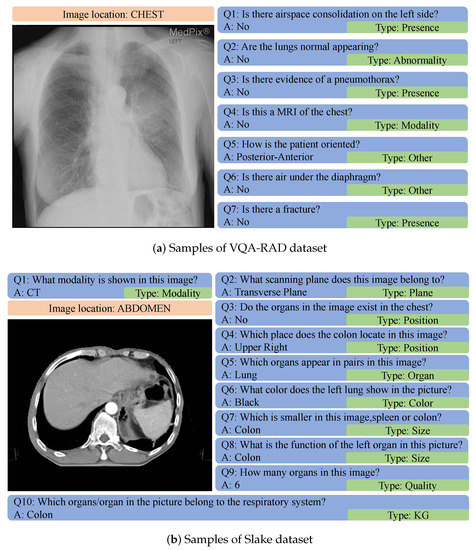

- Lau, J.J.; Gayen, S.; Abacha, A.B.; Demner-Fushman, D. A dataset of clinically generated visual questions and answers about radiology images. Sci. Data 2018, 5, 1–10. [Google Scholar] [CrossRef]

- Liu, B.; Zhan, L.M.; Xu, L.; Ma, L.; Yang, Y.; Wu, X.M. SLAKE: A Semantically-Labeled Knowledge-Enhanced Dataset for Medical Visual Question Answering. In Proceedings of the 2021 IEEE 18th International Symposium on Biomedical Imaging, Nice, France, 13–16 April 2021; pp. 1650–1654. [Google Scholar] [CrossRef]